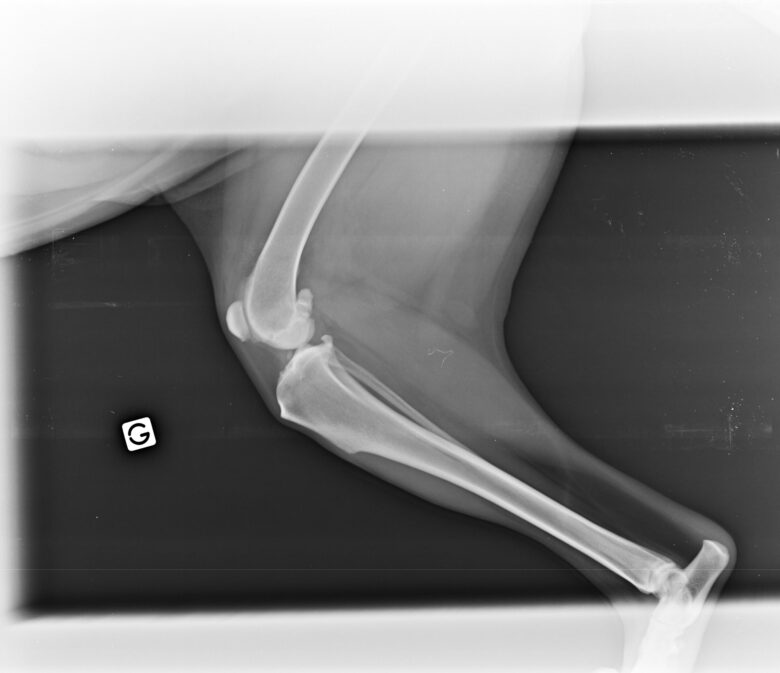

Nous avons choisi de faire une radio et c’est là que nous avons découvert l’impensable : Helly est atteinte d’une dysplasie très importante ainsi que d’arthrose et de becs de perroquet – les vertèbres se soudent entre elles et réduisent drastiquement la mobilité – à de multiples endroits.

L’intervention dure 30 à 40 minutes avec une sédation légère – ils n’intubent pas le chien a priori sauf exception – et le vétérinaire va venir déposer avec une grosse aiguille les implants d’or sur les zones prédéfinies. Helly a reçu 32 implants au total sur les hanches, la colonne et les poignets. A la Yourte, ils ne rasent que les zones nécessaires contrairement à d’autres cliniques qui rasent intégralement les hanches du chien par exemple.

Lors du contrôle post-opératoire de juillet 2025, le spécialiste constatait une belle amélioration de la mobilité sur la colonne mais plus timide sur les hanches, la zone la plus touchée. Rappelons que les effets sont évolutifs et progressifs dans le temps et qu’à 3 mois de l’opération, c’était donc parfaitement normal. En décembre 2025, constatant toujours quelques raideurs du train arrière notamment avec la période et les sorties hivernales, nous avons opté pour le laser en complément des implants. Après la 4ème séances de laser en janvier, Helly est en forme et ne présente pas de boiterie en revenant des sorties. D’ailleurs nous n’en avons jamais eu de nouvelles après la fameuse sortie de ski de rando à fond les ballons à 6 ans. Elle peut toujoursavoir des raideurs à froid en rentrant d’une grosse sortie mais le lendemain tout va bien.

Lors du contrôle post-opératoire de février 2026, soit 10 mois après la pause des implants, les hanches ont une véritable amélioration. Il reste un point très douloureux au centre de la colonne, point névralgique des mouvements entre les muscles de l’avant et de l’arrière, que l’on surveille. Il nous a été conseillé de masser régulièrement pour détendre les muscles sur cette zone.